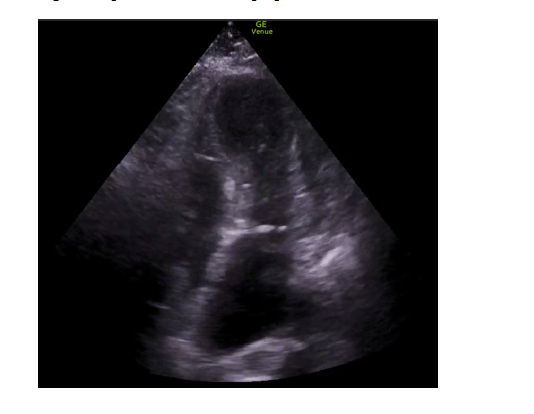

Antecedentes personales: HTA y obesidad.Como prueba complementaria se realizó un electrocardiograma que mostró elevación del ST en V1-V2 con T negativas en V3-V4-V5-V6. Posteriormente se trasladó a hospital de referencia, donde presentó marcadores de daño miocárdico elevados (troponinas: 171 ng/L). Se realizó coronariografía de urgencia a su llegada donde se descartan lesiones o estenosis en TCI/DA/Cx/CD. Previo al ingreso, se realizó ecocardiografía clínica por parte del servicio de urgencias y se visualizó imagen característica de dicho síndrome con abombamiento apical, la ventriculografía izquierda presentó discinesia medio-apical en todos los segmentos. Hipercontractilidad basal. IM ligera-moderada. Por tanto, se planteó como probable diagnóstico síndrome de Takotsubo y se descartaron otras posibles causas como derrame pericárdico.

En la actualidad, no hay suficiente evidencia sobre el manejo inicial, diagnóstico y tratamiento del síndrome de Takotsubo. Por esta razón, los informes de casos son muy útiles, ya que pueden ayudar a reconocer la existencia de este síndrome y considerarlo en el diagnóstico de pacientes con síndrome coronario agudo, además de contribuir a ampliar el conocimiento sobre su manejo. La ecocardiografía realizada en el servicio de urgencias puede ser útil para respaldar el diagnóstico, evaluando la extensión, gravedad y localización de las anomalías en el movimiento de las paredes del corazón, así como para detectar posibles complicaciones asociadas al síndrome de Takotsubo.